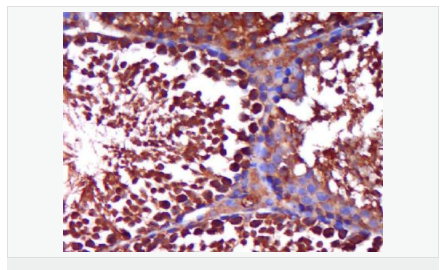

| 產品應用 | WB=1:500-2000 ELISA=1:5000-10000 IHC-P=1:100-500 IHC-F=1:100-500 Flow-Cyt=1ug/Test IF=1:100-500 (石蠟切片需做抗原修復) not yet tested in other applications. optimal dilutions/concentrations should be determined by the end user. |

| 產品介紹 | The androgen receptor gene is more than 90 kb long and codes for a protein that has 3 major functional domains: the N-terminal domain, DNA-binding domain, and androgen-binding domain. The protein functions as a steroid-hormone activated transcription factor. Upon binding the hormone ligand, the receptor dissociates from accessory proteins, translocates into the nucleus, dimerizes, and then stimulates transcription of androgen responsive genes. This gene contains 2 polymorphic trinucleotide repeat segments that encode polyglutamine and polyglycine tracts in the N-terminal transactivation domain of its protein. Expansion of the polyglutamine tract causes spinal bulbar muscular atrophy (Kennedy disease). Mutations in this gene are also associated with complete androgen insensitivity (CAIS). Two alternatively spliced variants encoding distinct isoforms have been described. [provided by RefSeq, Jul 2008] Function: Steroid hormone receptors are ligand-activated transcription factors that regulate eukaryotic gene expression and affect cellular proliferation and differentiation in target tissues. Transcription factor activity is modulated by bound coactivator and corepressor proteins. Transcription activation is down-regulated by NR0B2. Activated, but not phosphorylated, by HIPK3 and ZIPK/DAPK3. [ENZYME REGULATION] AIM-100 (4-amino-5,6-biaryl-furo[2,3-d]pyrimidine) suppresses TNK2-mediated phosphorylation at Tyr-267. Inhibits the binding of the Tyr-267 phosphorylated form to androgen-responsive enhancers (AREs) and its transcriptional activity. Subunit: Binds DNA as a homodimer. Part of a ternary complex containing AR, EFCAB6/DJBP and PARK7. Interacts with HIPK3 and NR0B2 in the presence of androgen. The ligand binding domain interacts with KAT7/HBO1 in the presence of dihydrotestosterone. Interacts with EFCAB6/DJBP, PELP1, PQBP1, RANBP9, RBAK, SPDEF, SRA1, TGFB1I1, ZNF318 and RREB1. Interacts with ZMIZ1/ZIMP10 and ZMIZ2/ZMIP7 which both enhance its transactivation activity. Interacts with SLC30A9 and RAD54L2/ARIP4. Interacts via the ligand-binding domain with LXXLL and FXXLF motifs from NCOA1, NCOA2, NCOA3, NCOA4 and MAGEA11. The AR N-terminal poly-Gln region binds Ran resulting in enhancement of AR-mediated transactivation. Ran-binding decreases as the poly-Gln length increases. Interacts with HIP1 (via coiled coil domain). Interacts (via ligand-binding domain) with TRIM68. Interacts with TNK2. Interacts with USP26. Interacts with RNF6. Interacts (regulated by RNF6 probably through polyubiquitination) with RNF14; regulates AR transcriptional activity. Interacts with PRMT2 and TRIM24. Interacts with GNB2L1/RACK1. Interacts with RANBP10; this interaction enhances dihydrotestosterone-induced AR transcriptional activity. Interacts with PRPF6 in a hormone-independent way; this interaction enhances dihydrotestosterone-induced AR transcriptional activity. Interacts with STK4/MST1. Interacts with ZIPK/DAPK3. Interacts with LPXN. Interacts with MAK. Part of a complex containing AR, MAK and NCOA3. Subcellular Location: Nucleus. Cytoplasm. Note=Predominantly cytoplasmic in unligated form but translocates to the nucleus upon ligand-binding. Can also translocate to the nucleus in unligated form in the presence of GNB2L1. Tissue Specificity: Isoform 2 is mainly expressed in heart and skeletal muscle. Post-translational modifications: Sumoylated on Lys-386 (major) and Lys-520. Ubiquitinated. Deubiquitinated by USP26. 'Lys-6' and 'Lys-27'-linked polyubiquitination by RNF6 modulates AR transcriptional activity and specificity. Phosphorylated in prostate cancer cells in response to several growth factors including EGF. Phosphorylation is induced by c-Src kinase (CSK). Tyr-534 is one of the major phosphorylation sites and an increase in phosphorylation and Src kinase activity is associated with prostate cancer progression. Phosphorylation by TNK2 enhances the DNA-binding and transcriptional activity and may be responsible for androgen-independent progression of prostate cancer. Phosphorylation at Ser-81 by CDK9 regulates AR promoter selectivity and cell growth. Phosphorylation by PAK6 leads to AR-mediated transcription inhibition. Palmitoylated by ZDHHC7 and ZDHHC21. Palmitoylation is required for plasma membrane targeting and for rapid intracellular signaling via ERK and AKT kinases and cAMP generation. DISEASE: Defects in AR are the cause of androgen insensitivity syndrome (AIS) [MIM:300068]; previously known as testicular feminization syndrome (TFM). AIS is an X-linked recessive form of pseudohermaphroditism due end-organ resistance to androgen. Affected males have female external genitalia, female breast development, blind vagina, absent uterus and female adnexa, and abdominal or inguinal testes, despite a normal 46,XY karyotype. Defects in AR are the cause of spinal and bulbar muscular atrophy X-linked type 1 (SMAX1) [MIM:313200]; also known as Kennedy disease. SMAX1 is an X-linked recessive form of spinal muscular atrophy. Spinal muscular atrophy refers to a group of neuromuscular disorders characterized by degeneration of the anterior horn cells of the spinal cord, leading to symmetrical muscle weakness and atrophy. SMAX1 occurs only in men. Age at onset is usually in the third to fifth decade of life, but earlier involvement has been reported. It is characterized by slowly progressive limb and bulbar muscle weakness with fasciculations, muscle atrophy, and gynecomastia. The disorder is clinically similar to classic forms of autosomal spinal muscular atrophy. Note=Caused by trinucleotide CAG repeat expansion. In SMAX1 patients the number of Gln ranges from 38 to 62. Longer expansions result in earlier onset and more severe clinical manifestations of the disease. Note=Defects in AR may play a role in metastatic prostate cancer. The mutated receptor stimulates prostate growth and metastases development despite of androgen ablation. This treatment can reduce primary and metastatic lesions probably by inducing apoptosis of tumor cells when they express the wild-type receptor. Defects in AR are the cause of androgen insensitivity syndrome partial (PAIS) [MIM:312300]; also known as Reifenstein syndrome. PAIS is characterized by hypospadias, hypogonadism, gynecomastia, genital ambiguity, normal XY karyotype, and a pedigree pattern consistent with X-linked recessive inheritance. Some patients present azoospermia or severe oligospermia without other clinical manifestations. Similarity: Belongs to the nuclear hormone receptor family. NR3 subfamily. Contains 1 nuclear receptor DNA-binding domain. SWISS: P10275 Gene ID: 367 Database links: Entrez Gene: 367 Human Entrez Gene: 11835 Mouse Omim: 313700 Human SwissProt: P10275 Human SwissProt: P19091 Mouse Unigene: 496240 Human Unigene: 39005 Mouse Unigene: 394224 Mouse Unigene: 439657 Mouse Unigene: 9813 Rat Important Note: This product as supplied is intended for research use only, not for use in human, therapeutic or diagnostic applications. AR是一個由917個氨基酸組成的蛋白質,位于雄激素靶組織細胞中或細胞表面上的特異分子部位或結構。 AR在前列腺癌中起著重要的作用,研究表明AR的表達與組織分型形成一定的相關性 ,AR在高分化的腫瘤中表達較多,而在低分化的腫瘤中表達較少。用于前列腺癌的檢測,指導臨床治療,目前可用于乳腺癌、食道癌等各項腫瘤的研究。 |